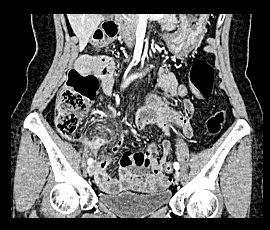

[急性虫垂炎] 手術:腹腔鏡下虫垂切除術(虫垂周囲膿瘍を伴う)

急性腹症のため救急受診。精査の結果、急性虫垂炎と診断。緊急手術(虫垂周囲膿瘍を伴う腹腔鏡下虫垂切除術)を施行した。病理診断結果は急性化膿性虫垂炎であった。

CT画像